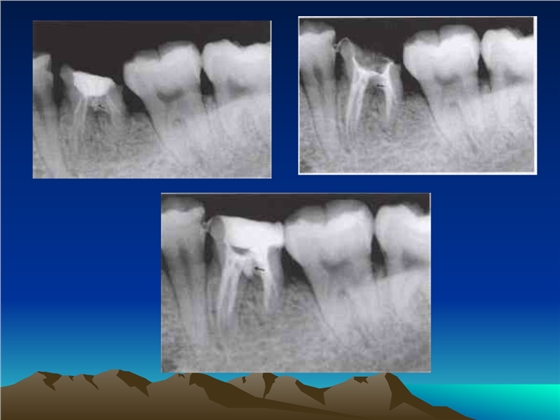

鈣化細(xì)小根管的處理技巧